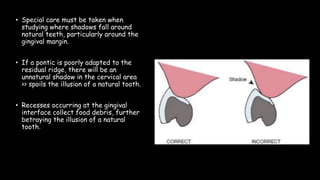

The document discusses pontic design for fixed dental prostheses. It covers pretreatment assessment of residual ridge contours, classifications of ridge deformities, surgical modification techniques, and ideal requirements for pontics. Pontic designs are classified based on their shape and materials. Factors in pontic selection include esthetics and oral hygiene. Common designs for anterior and posterior regions are described, including sanitary, ovate, and saddle pontics. Biological considerations for pontic design involve maintaining the residual ridge, abutment teeth, and supporting tissues.